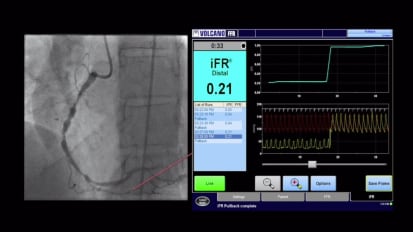

Optimizing coronary stenting: the role of IVUS in today’s precision PCI

Hear Dr. Jimmy Kerrigan and Dr. Lorenzo Azzalini as they discuss the role of intravascular imaging in their practice and how the utility of routine IVUS can guide procedural planning and optimization of treatment. This program highlights the clinical utility and benefits of IVUS through a review of current clinical data, including the ULTIMATE trial, and through demonstration and discussion of IVUS in a variety of clinical scenarios.